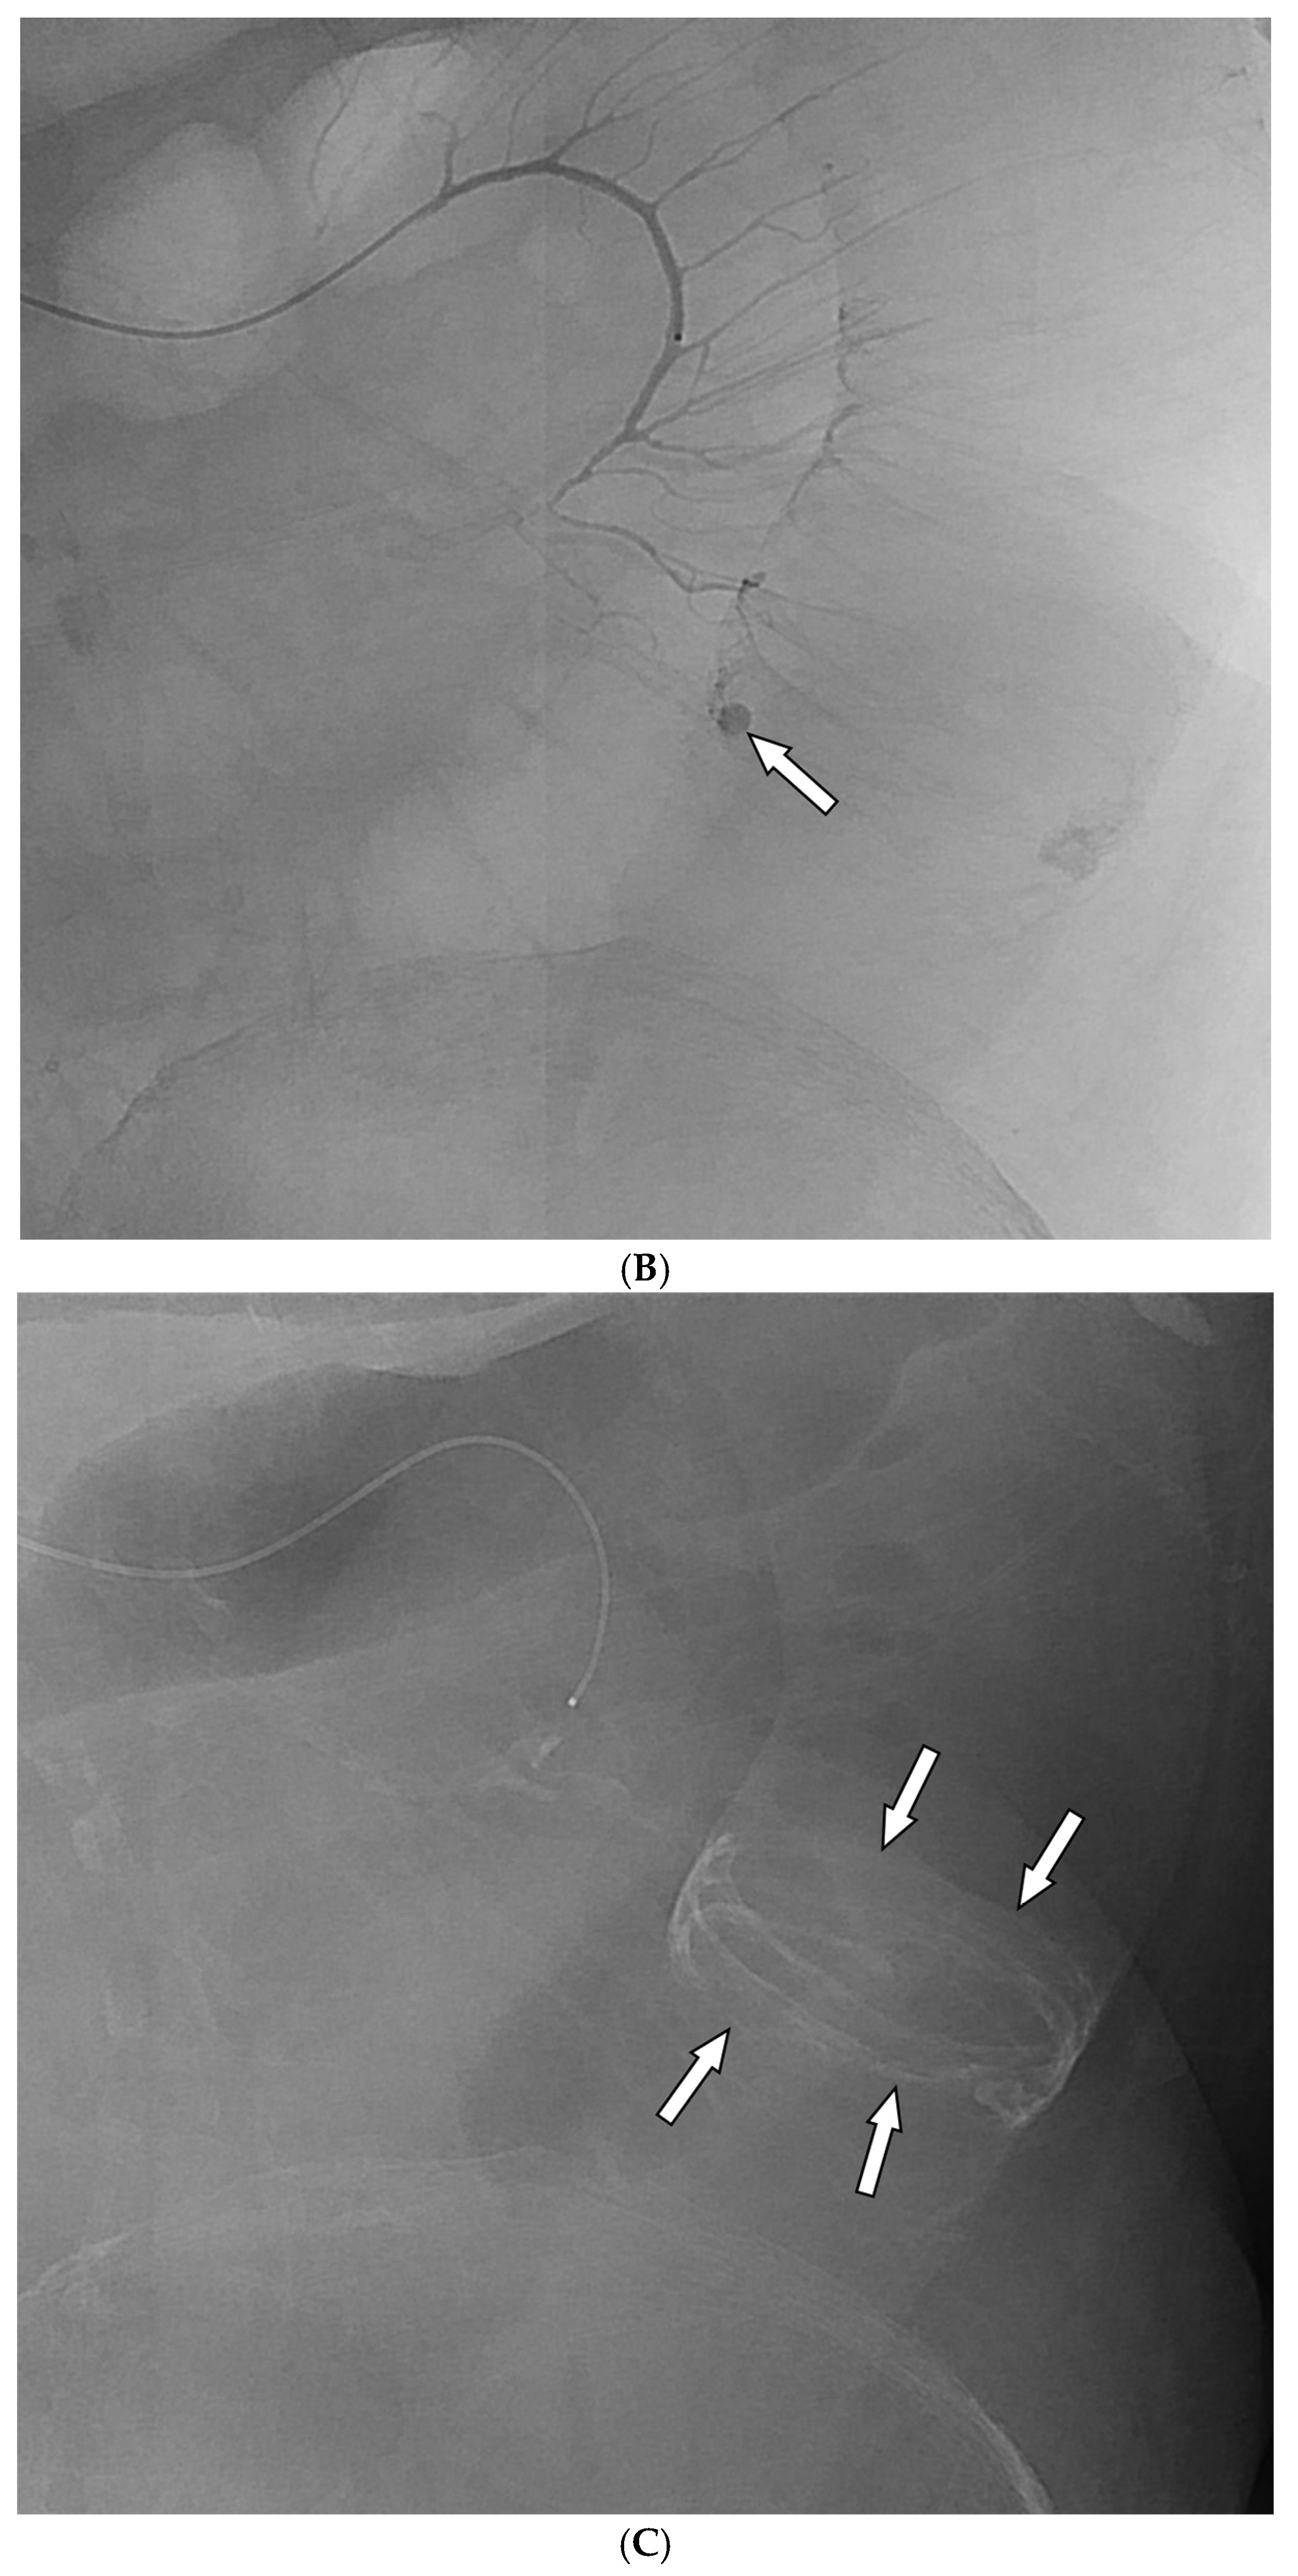

Figure 3. A 59-year-old man with colonic diverticula presented with hematochezia. (A) Contrast-enhanced axial CT image shows colonic diverticula with luminal contrast extravasation (arrow) at the hepatic flexure. Sigmoidoscopy performed one day after the CT scan reveals a diverticulum with bleeding (inset). Endoscopic hemoclipping was performed (not shown). (B) Superior mesenteric arteriography demonstrates focal hypervascularity (arrows) around the endoclipping site, without evidence of contrast extravasation. As superselection was not possible, the arterial branches leading to the endoclipping site were embolized using quick-soluble gelatin sponge particles (150–350 µm). (C) Post-embolization arteriography shows marked reduction in the previously observed hypervascularity around the endoclipping site. (D) Sigmoidoscopy performed two days after embolization reveals several ulcers and erythematous changes around the hemoclipping site, consistent with ischemic colitis. Associated abdominal pain resolved within three days. No further bleeding occurred during the 6-month follow-up.